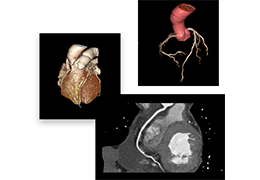

ART-Plan™ Artificial Intelligence Contouring